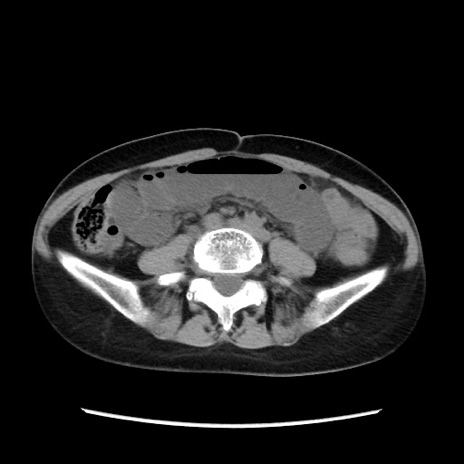

症例32(横断像)

【症例】40歳代 女性

【主訴】上腹部痛、嘔気・嘔吐

【現病歴】約9時間前頃から急に上腹部痛、嘔気、嘔吐が出現。改善しないため救急要請。

【既往歴】子宮頚癌(広汎子宮全摘術、放射線療法)、腸閉塞

【身体所見】腹部:平坦、軟、腸雑音亢進、上腹部を中心に腹部全体に圧痛あり。

【データ】WBC 8400、CRP 0.03